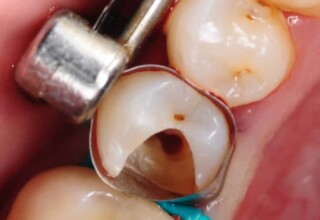

Αποκατάσταση Ραγισμένου Γομφίου με σφράγισμα Σύνθετης Ρητίνης

Τα ραγισμένα δόντια αποτελούν μια πρόκληση για την επανορθωτική οδοντιατρική από την άποψη της δυσκολίας της αποκατάστασης(συνήθως μεγάλα σφραγίσματα) άλλα κυρίως από τα προληπτικά μετρά που πρέπει να παρθούν για να αποφευχθεί ένα πλήρες κάταγμα. Η ακόλουθη περίπτωση παρουσιάζει την απλούστερη προσέγγιση της άμεσης συγκολλούμενης αποκατάστασης από σύνθετη ρητίνη. Βασίζεται στο σκεπτικό ενός συγκολούμμενου σφραγίσματος που «κρατάει» τα εναπομείναντα οδοντικά τμήματα «ενωμένα». Ο συγκεκριμένος γομφίος παρέμεινε ακέραιος για δυο χρονιά, οπότε χρειάστηκε απονεύρωση γιατί νεκρώθηκε και κατόπιν τοποθετήθηκε στεφάνη για αυξημένη προστασία.